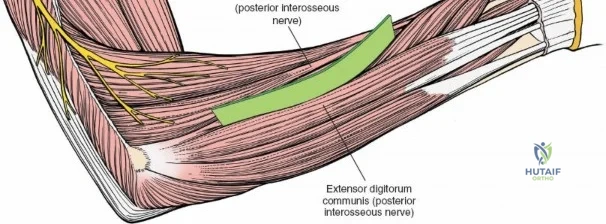

The Posterior Interosseous Nerve (PIN)

The posterior interosseous nerve is the single most important structure left vulnerable during exposure of the proximal radius. A branch of the radial nerve, the PIN dives into the supinator muscle through the Arcade of Frohse. It travels obliquely and spirally around the radial neck and proximal shaft within the substance of the supinator. In approximately 25% of patients, the nerve comes into direct contact with the posterior periosteum of the radial neck. Therefore, any blind placement of retractors around the posterior aspect of the proximal radius is strictly contraindicated, as it can easily crush the nerve against the bone, resulting in devastating loss of finger and thumb extension.

The proximal radius is draped by the supinator muscle. The PIN passes directly through the belly of the supinator. To protect the nerve, the forearm must be fully supinated. Supination dynamically rotates the radius, carrying the insertion of the supinator anteriorly and simultaneously displacing the PIN laterally and posteriorly, safely away from the surgical field.

With the forearm fully supinated, identify the broad insertion of the supinator on the anterior aspect of the radius. Incise the supinator directly along the line of its insertion onto the bone. It is critical to detach the muscle by dividing its insertion sharply at the bone, rather than splitting the muscle belly, which would risk cutting the PIN.

Proceed with strict subperiosteal dissection, elevating the supinator laterally off the bone. This is one of the rare instances in orthopedic surgery where the safety gained by staying in a subperiosteal plane completely outweighs the theoretical vascular damage to the bone caused by periosteal stripping. The elevated supinator muscle belly now acts as a protective cushion for the PIN.